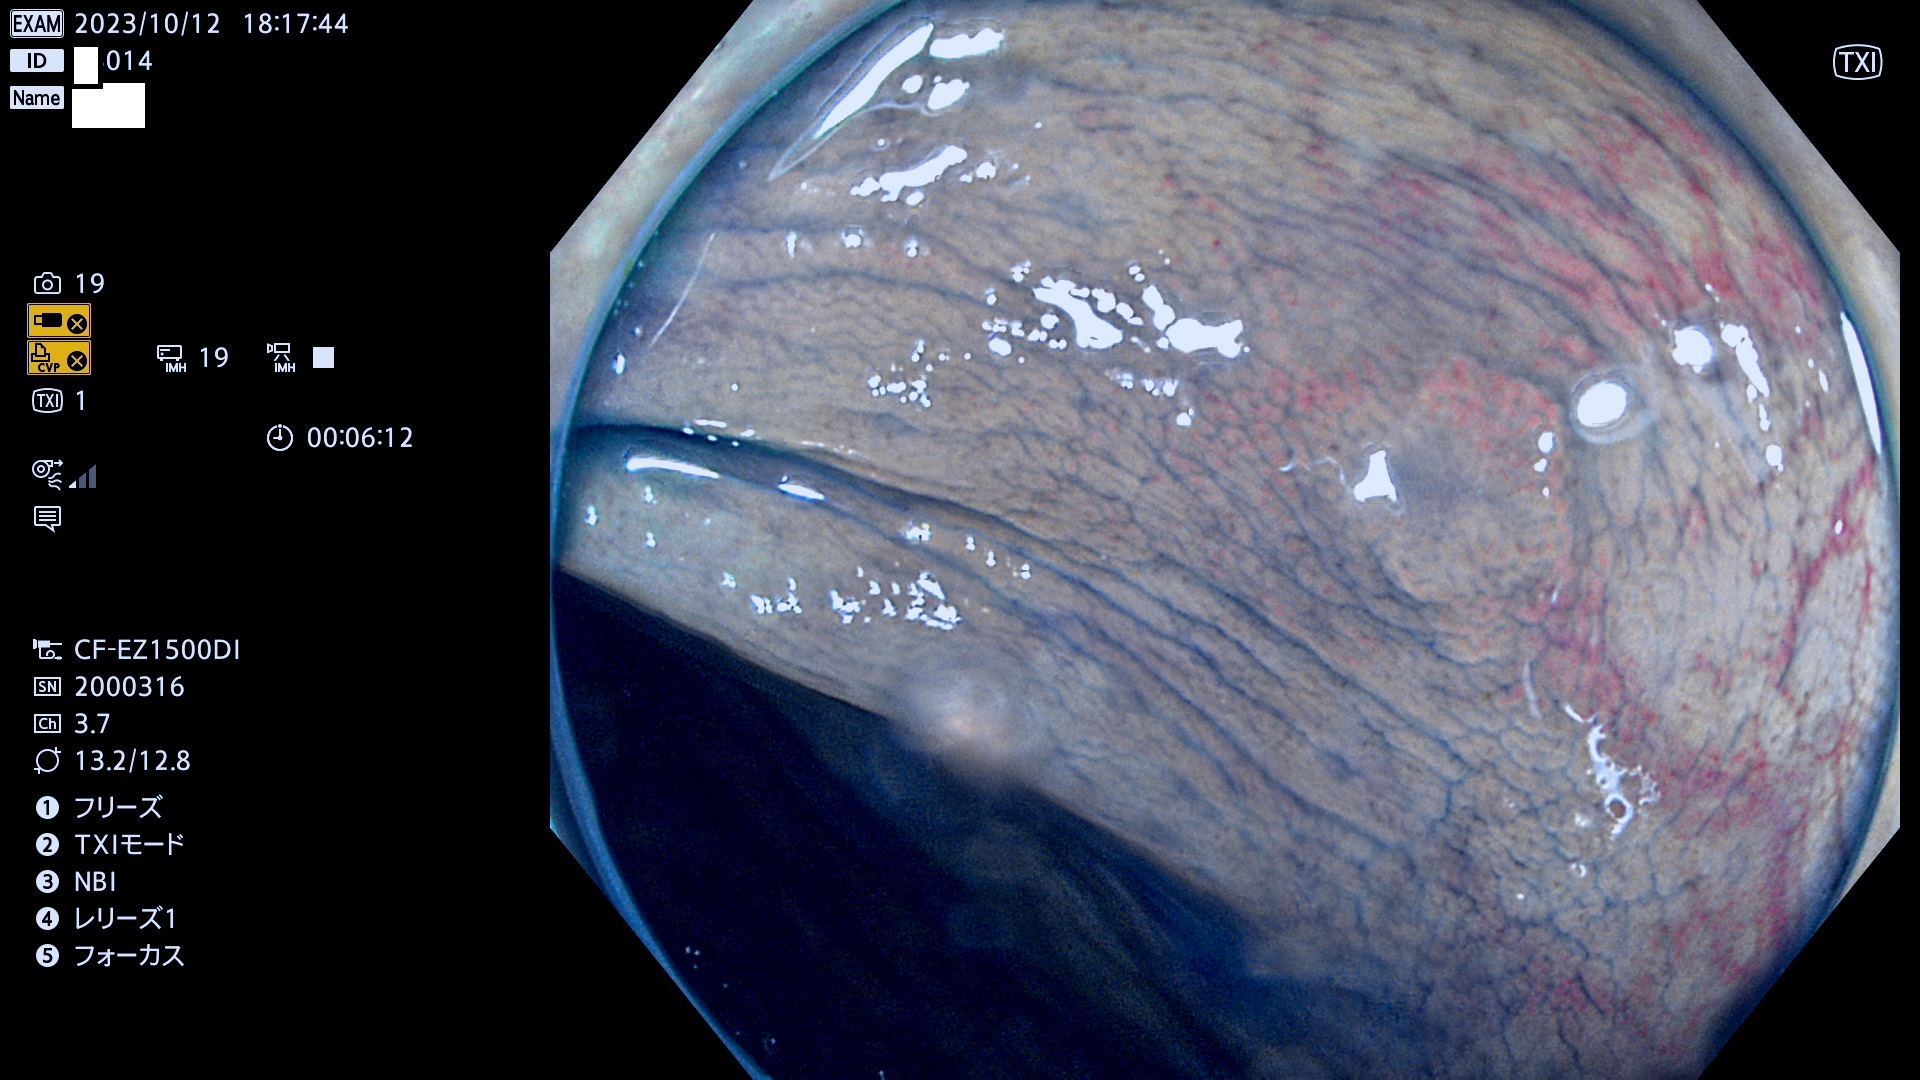

表面型腺腫(Flat Adenoma)の中で、完全に平坦な物をUb、陥凹している物をUcと呼びます。平坦隆起型(Ua)よりも、発見が難しく危険な病変です。このタイプは「内視鏡後・大腸癌の重要犯人」であり、この発見率は「腺腫発見率」よりも、重要な意味があります。

毎週の検査(木・金・土・日)に発見されたUb、Uc型・腺腫を、その週の日曜の夜にUPし1週間、提示します。

抽出の対象期間 2023年10月12日(木)〜10月15(日)の5日間(48件の検査)4件